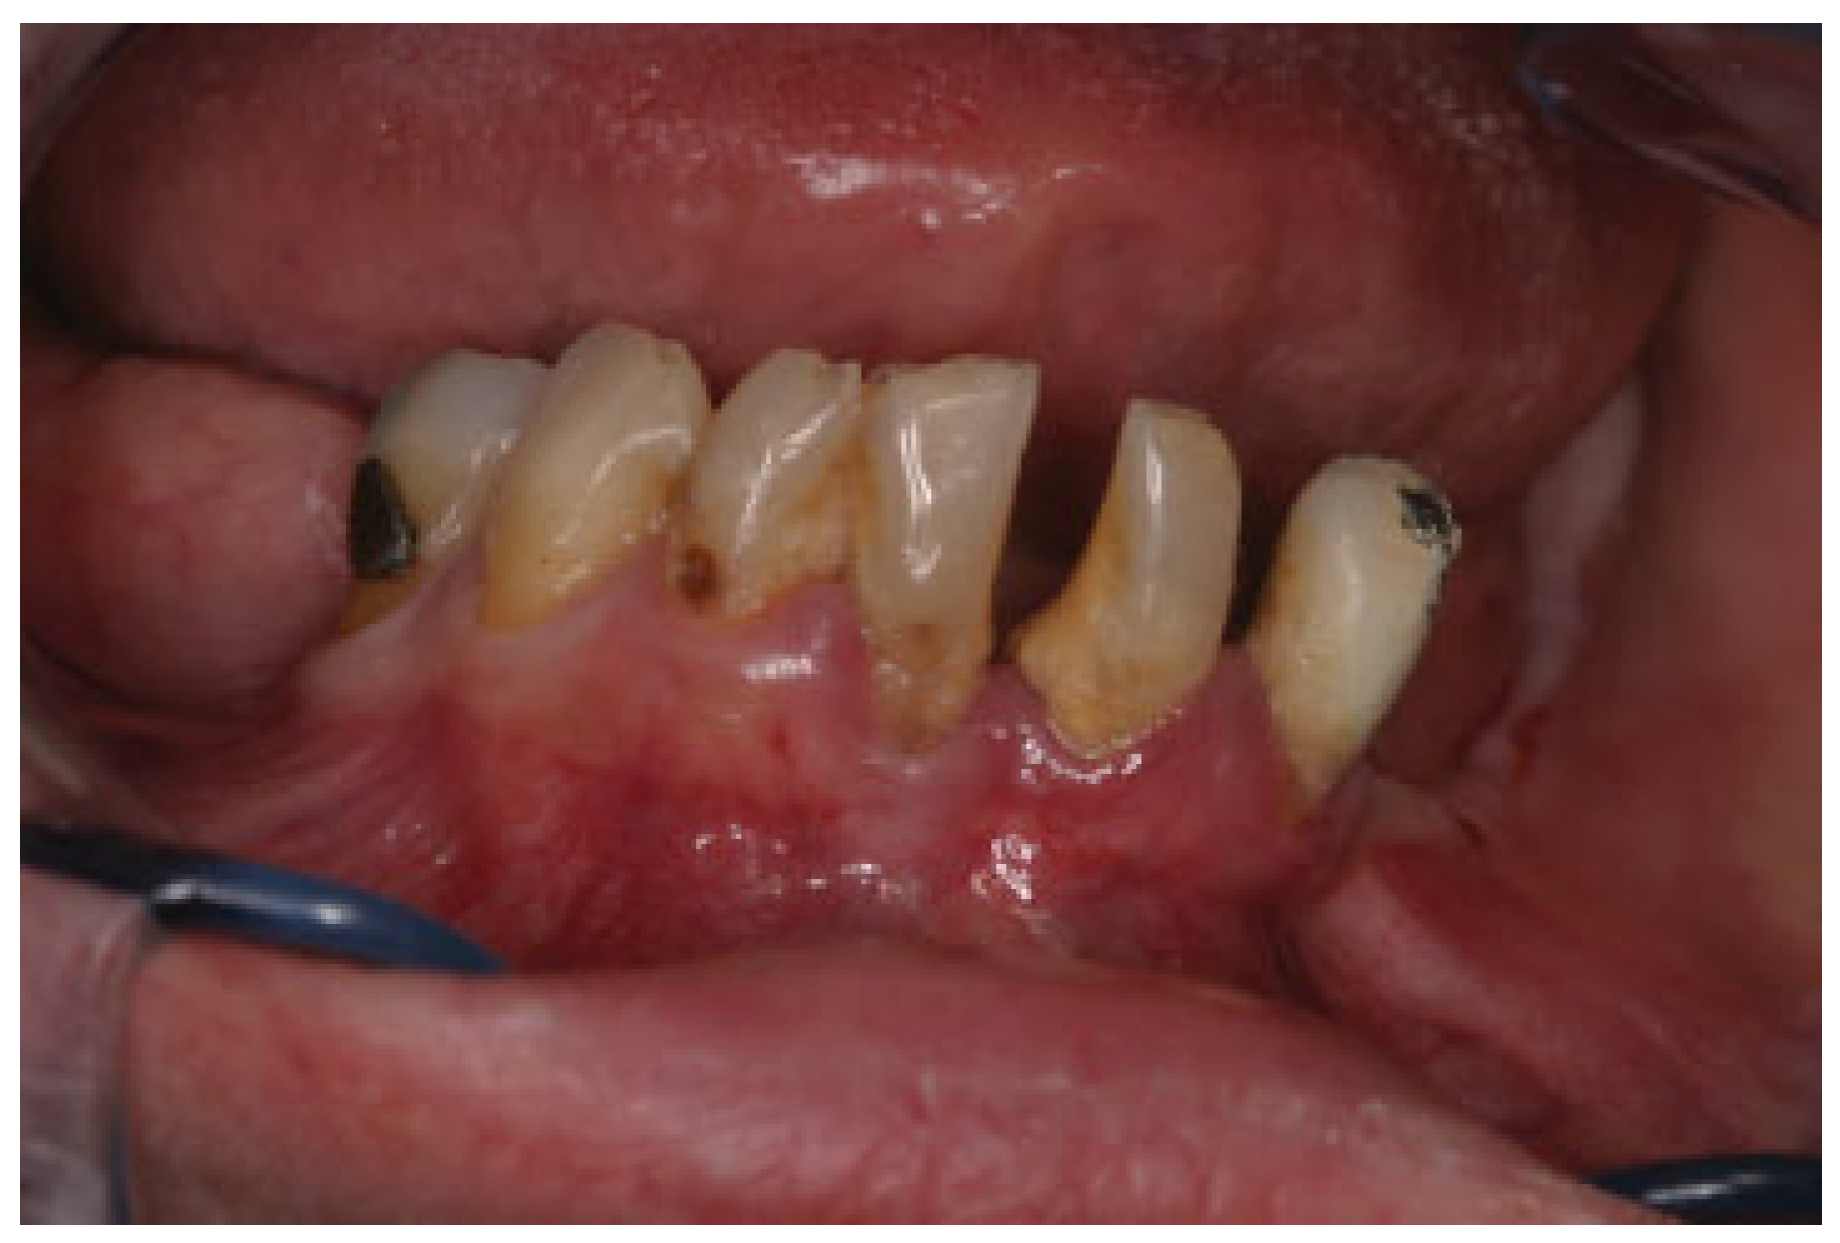

Clinical Report

Figure 1. Severely resorbed bilateral posterior edentulous mandible and periodontal disease and calculus on the remaining teeth.